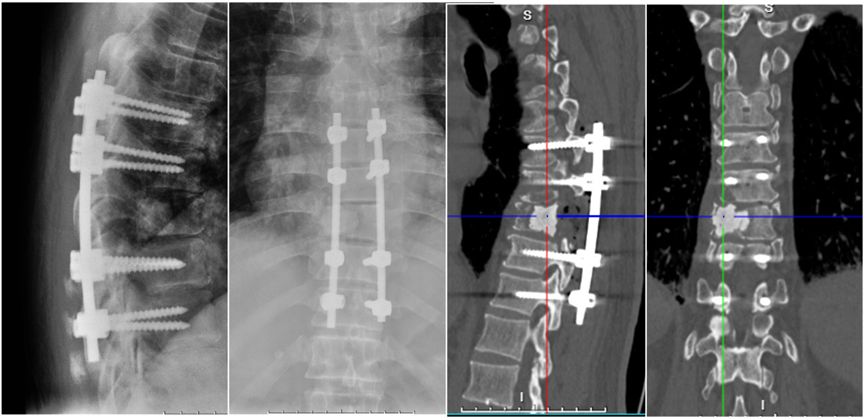

1. 手术治疗: 2025年6月17日,患者在全麻下行T9脊髓减压+经椎弓根螺钉内固定术(T7-T11),术中见T9椎体明显破坏,脊髓受压,予以肿瘤减压及稳定固定(图3)。

图3. 术后复查X线和CT